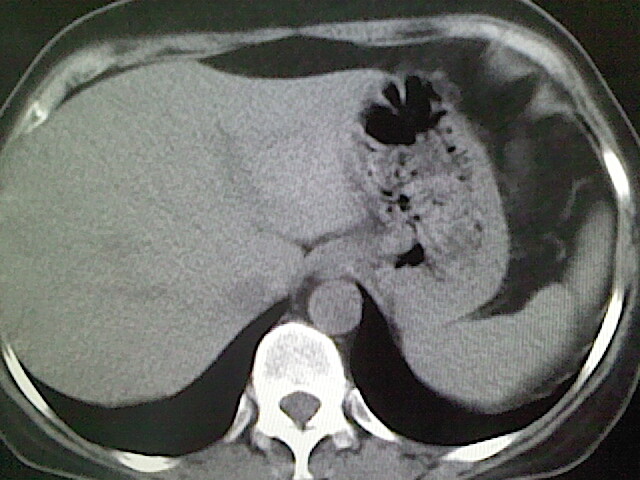

女,52岁,咳嗽,咳痰多日

左下肺陈旧纤维索条!

左肺舌段炎性改变

我见过几例,为炎症后纤维条索

慢性炎症后改变

考虑慢性炎性病灶粘连牵拉改变。

左肺舌叶纤维锁条病变。

左肺上叶下舌段炎症并局部胸膜反应。

左肺舌叶纤维索条影。

左肺舌叶段陈旧性病变

左肺舌段炎性反应。片子的质量太不好了。

左肺舌段炎性

炎性改变

左肺舌叶纤维索条影